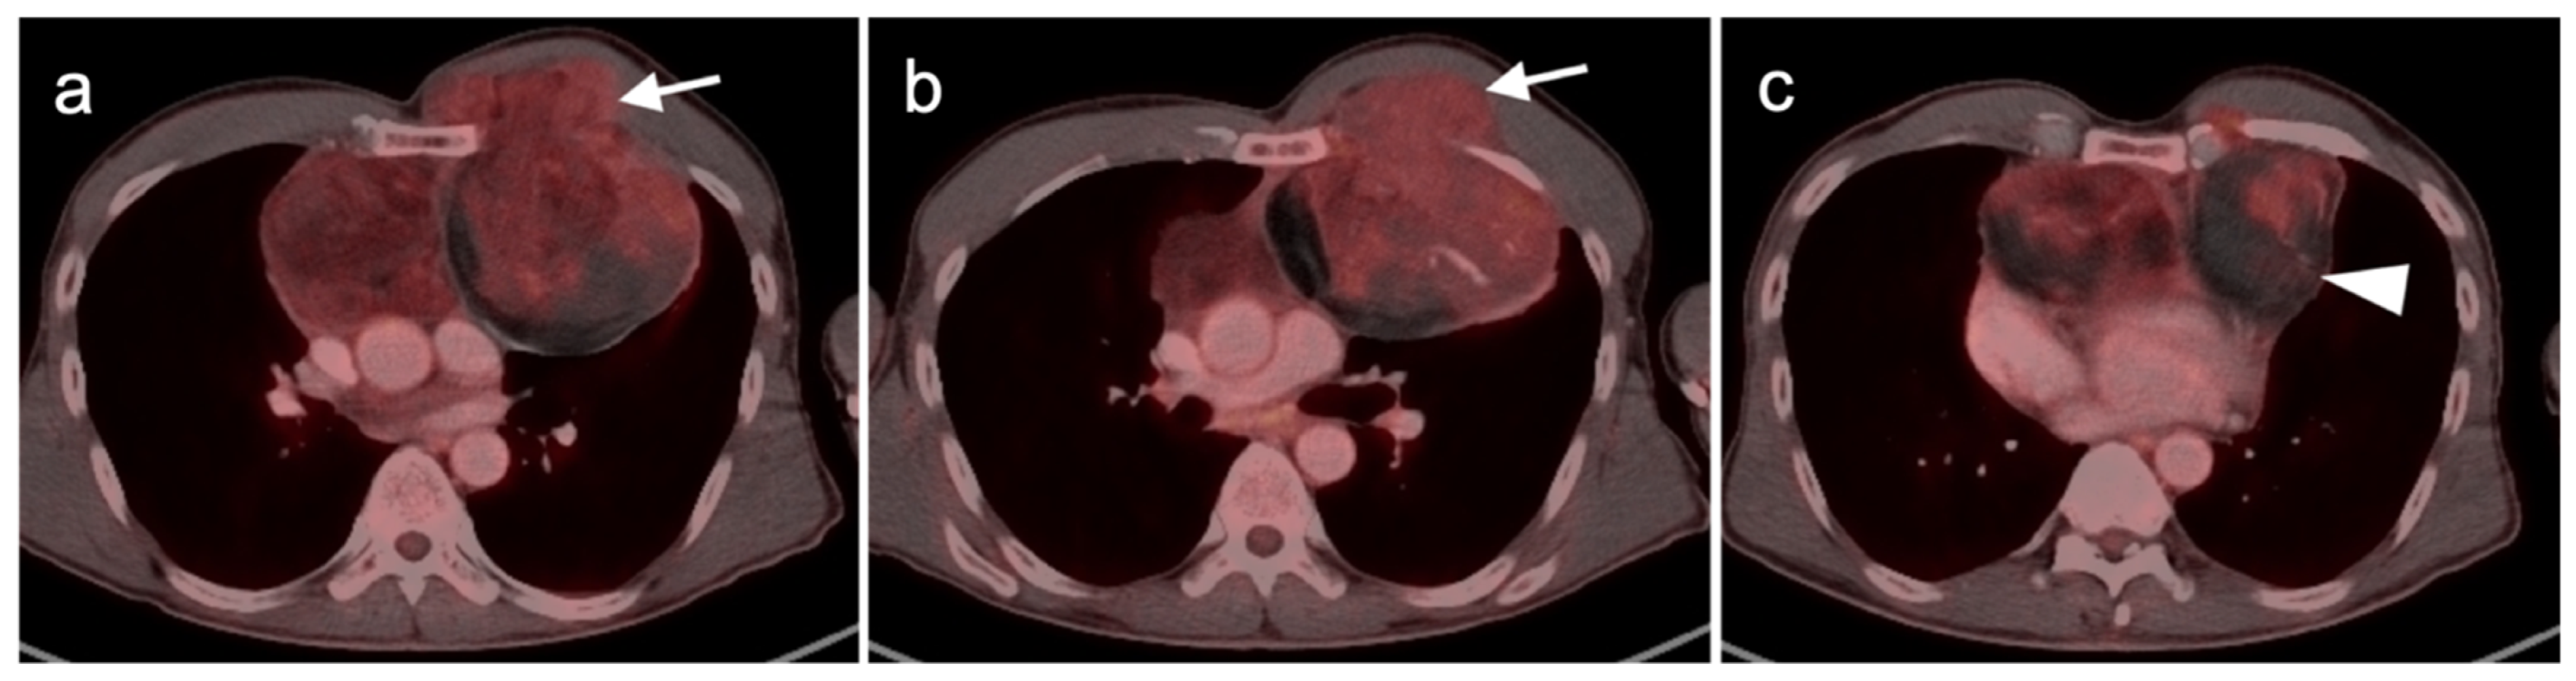

- Camoni, L.; Albano, D. Contrast-enhanced 18F-FDG PET/CT to differentiate primary cardiac lymphoma from primary cardiac angiosarcoma. J. Nucl. Cardiol. 2021, 1–3. [Google Scholar] [CrossRef]